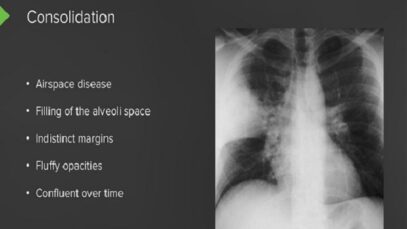

●High resolution computed tomography (HRCT, also called thin-section CT scanning) provides more detail than either chest radiography or conventional CT scanning, with an overall sensitivity of 95 percent and a specificity approaching 100 percent. Compared to chest radiography, HRCT can more accurately assess the pattern and distribution of diffuse lung disease, which may be beneficial […]